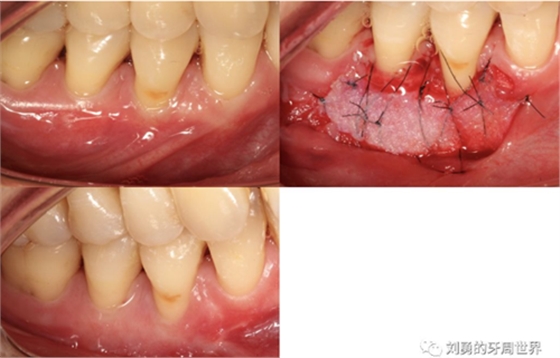

比如strip技術(shù),如下圖:

上圖中,種植體唇側(cè)缺乏附著齦,從上腭取瓣,常規(guī)做法:取長而寬的齦瓣,這樣供區(qū)面積大,術(shù)后疼痛重。

為了減少痛感,從雙側(cè)上腭取多條長而窄的齦瓣進(jìn)行移植,這樣每個供區(qū)的傷口都比較窄,可以減少術(shù)后的痛感。

可見右上前牙植體頰側(cè)無附著齦

為了減少取瓣大小,從上腭取厚一點的齦瓣,然后用刀片平行于表皮表面將齦瓣片切成兩個厚度一致的齦瓣,然后進(jìn)行移植,這樣切成的兩個齦瓣一個有表皮,一個沒有表皮是單純的結(jié)締組織。如此的片切可以使齦瓣變成雙倍的大小使用,減少了供區(qū)的取瓣面積。